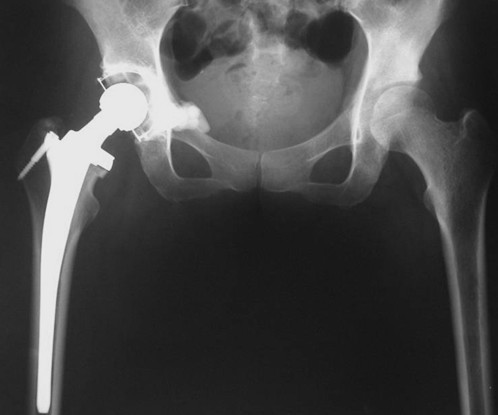

本组病例中不同部位髋臼转移癌的手术方式(图1):I型:髋臼下壁骨破坏、上壁及内、外侧壁完整, 采用肿瘤刮除、普通水泥型全髋置换术。II型:髋臼内、外侧壁破坏,上壁骨质完整, 采用带翼网杯+水泥型全髋置换术。 III型:髋臼上壁及内、外侧壁均破坏,采用肿瘤刮除后、骨水泥填充髋臼上壁骨缺损,带翼网杯+水泥型全髋或组合式人工半骨盆。IV型:孤立性骨盆转移, 以治愈为目的, 采用肿瘤整块切除,组合式人工半盆置换术。

Ⅰ型:髋臼外侧皮质,上方及内侧壁完好,髋臼下及前后方破坏缺损。可以采用骨水泥固定的普通全髋置换术以达到长期牢固固定。手术入路一般采用后外侧入路,不需要大转子截骨,可在髋臼深部放置金属网以加强骨水泥的固定效果,阻挡股骨头向内移位。术后第一天病人即可在耐受范围内下地活动并完全负重。

图2,女,31岁,乳腺癌髋臼转移, Harrington I型